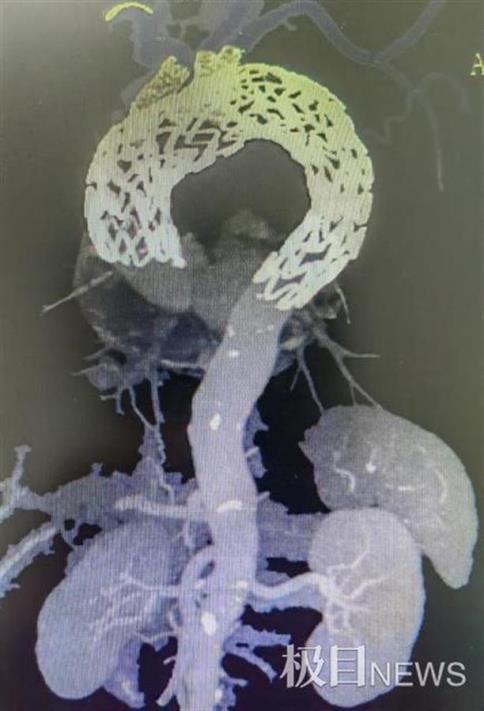

咽喉腫瘤亟需手術(shù)治愈,但是患者不幸又并發(fā)被動(dòng)脈血管瘤。這顆隨時(shí)都會(huì)引爆的炸彈,令醫(yī)患兩邊左右難堪。武漢大學(xué)人民醫(yī)院(湖北省人民醫(yī)院)血管內(nèi)科鄧宏平老師隊(duì)伍巧妙地應(yīng)用體外3D模型,在身體最大血管“三開窗”,順利征服較大被動(dòng)脈瘤,為后續(xù)腫瘤手術(shù)治愈奪取良機(jī)。

鄧宏平老師隊(duì)伍聯(lián)合超聲科周青老師隊(duì)伍十足討論,術(shù)前應(yīng)用了體外3D模型技巧,訂制模仿了邢爹爹的被動(dòng)脈弓部血管,這類“量身定做”技巧戰(zhàn)勝了被動(dòng)脈弓一些支支架開窗定位不準(zhǔn)的艱難,同時(shí)可變短手術(shù)時(shí)間,有效減低手術(shù)危害。4月底,隊(duì)伍施行“升被動(dòng)脈、被動(dòng)脈弓、降被動(dòng)脈支架植入+被動(dòng)脈弓部三分類血管開窗重建”的微創(chuàng)手術(shù)方法,順利阻隔了被動(dòng)脈弓部的瘤體。術(shù)后邢爹爹修復(fù)優(yōu)良。